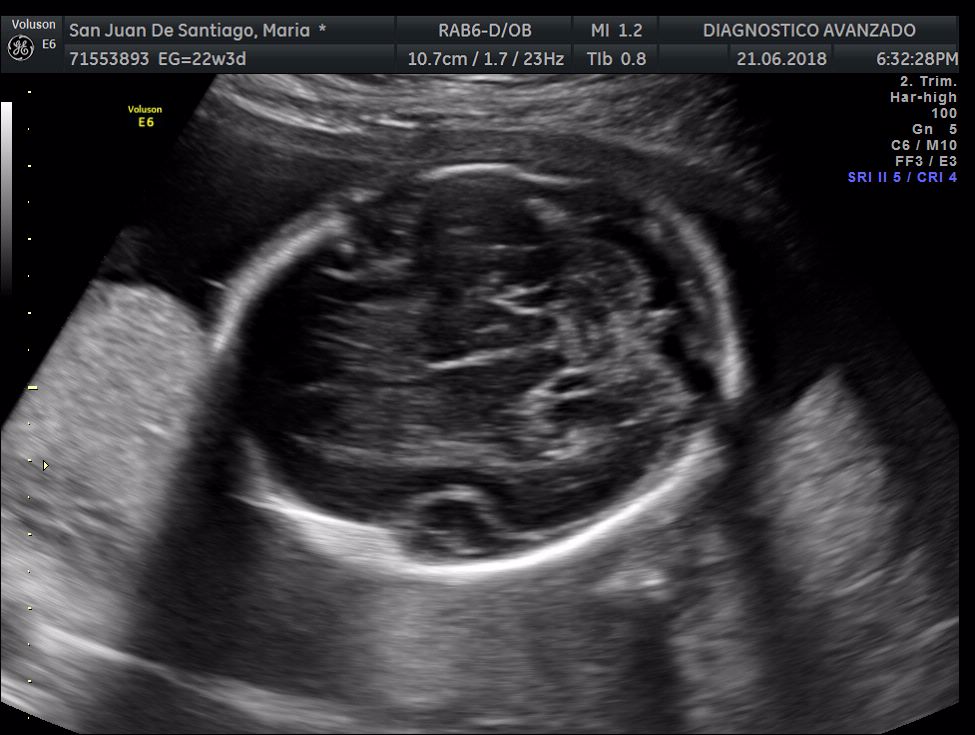

¡Hola a todos! Hoy hemos ido a hacer la tradicional ecografía 3D de la niña, os dejamos todo el material (aunque es un poco demasiado).